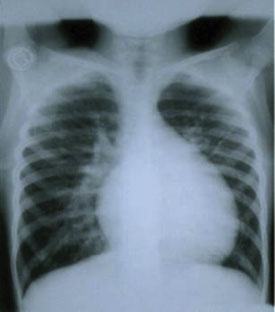

In the chest X-ray, the cardiac silhouette is normal or small with a raised cardiac apex and a reduced pulmonary arterial cone (resulting in a clog-shaped heart, see next image). The pulmonary vascularization is either normal or diminished.